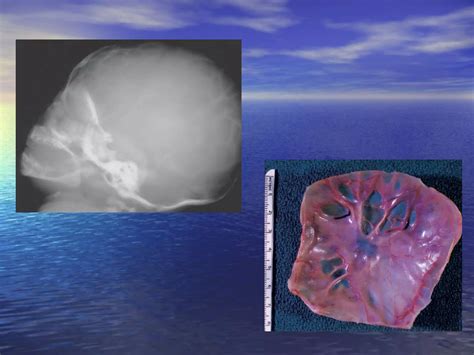

• Fractures: Visible cracks or breaks in the skull bones.

• Deformities: Abnormal shapes or structures of the skull.

• Infections: Signs of infection, such as bone erosion or swelling.

• Tumors: Abnormal growths or masses within the skull.

• Developmental Abnormalities: Issues with the development of the skull, such as premature fusion of sutures.

Each of these findings requires a different approach to treatment and care. Healthcare providers will use the X-ray results to develop a tailored plan for the baby’s health and well-being.